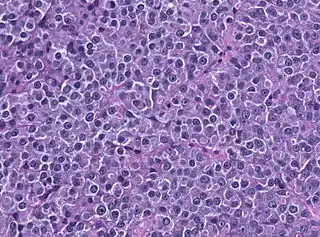

Se denomina prolactinoma[1] al tumor benigno secretor, compuesto por las células de la hipófisis que liberan prolactina, que presenta actividad productora y liberadora de dicha hormona, y que puede oprimir la glándula hipófisis.

Un prolactinoma es un tumor secretante (adenoma) de la adenohipófisis, cuyas células (los lactotropos) segregan Prolactina, esto produce concentraciones elevadas de esta hormona, condición denominada hiperprolactinemia.[2]

Los prolactinomas son tumores benignos, rara vez sufren transformación maligna o invasividad local. Se ha propuesto que los prolactinomas tienen un origen monoclonal y que las alteraciones en la regulación del ciclo celular conducen a la expansión de una célula original mutada.[3]